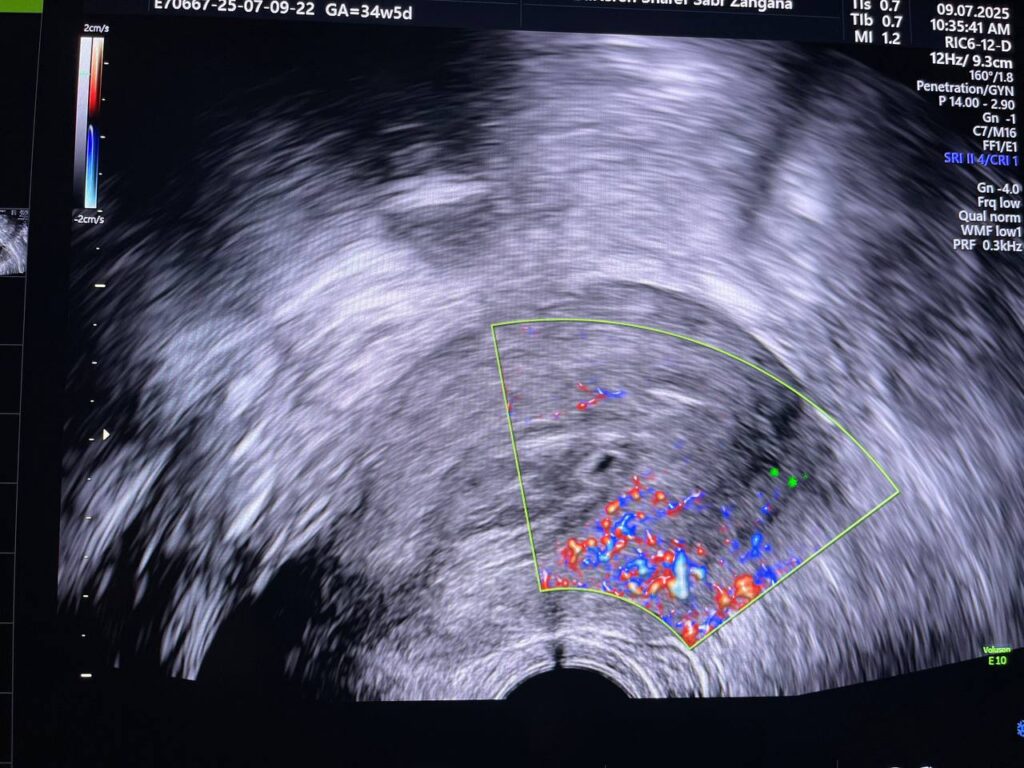

Bulky size, A/V uterus,  endometrial lining thickness 22mm, the cavity occupied by heterogenous avascular lesion 42x16mm , mostly blood clots? in addition to presence of few cysts with instinct  left anterior upper part of the endo myometrial junctional zone , in area size about 11.5x9mm, mostly remains of hydatiform wall  , please for further study   , no fibroid

This patient has high BHCG level , with History of H Mole on march 2025